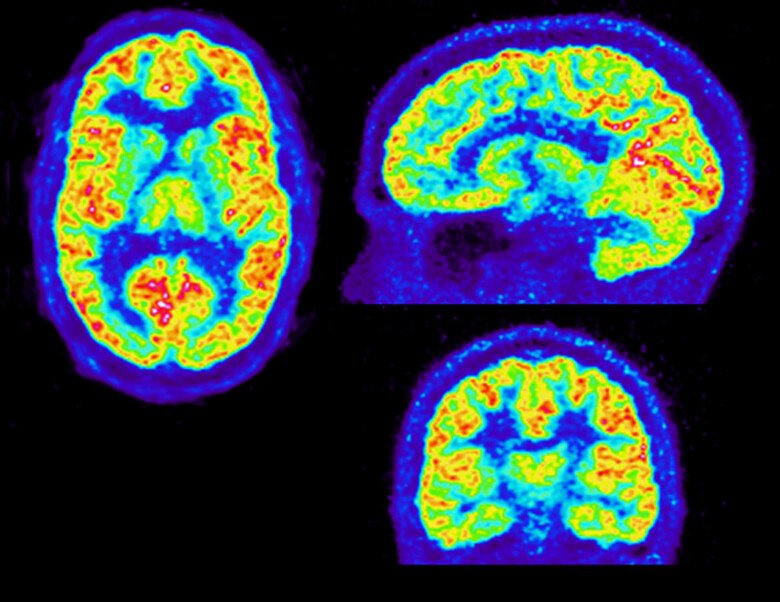

A Core Facility for molecular imaging of the brain using Positron Emission Tomography (PET).

Positron Emission Tomography (PET) is an unsurpassed method for imaging biochemical and physiological processes in vivo.